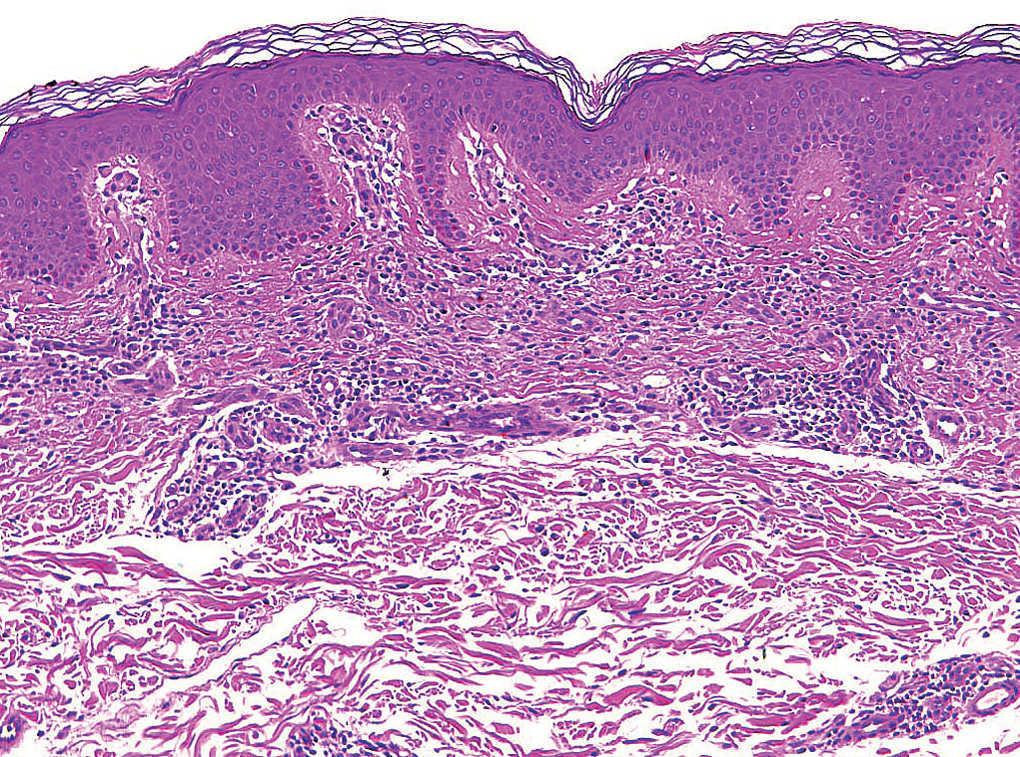

En todos los pacientes se realizaron biopsias cutáneas que mostraron hallazgos similares. Se identificaba un infiltrado intersticial en la dermis papilar y media por unas células muy monomorfas, de citoplasma redondo, con unos gránulos en su interior metacromáticos con la tinción de Giemsa (fig. 3). Estas células se identificaron como mastocitos (fig. 4).

Fig. 3.--Detalle del infiltrado de disposición liquenoide. Obsérvese la ausencia de epidermotropismo. (Hematoxilina-eosina, x40.)